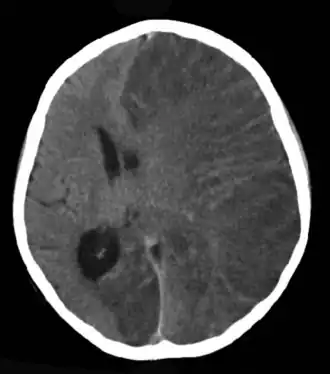

La epilepsia puede tener muchas causas. Puede tener origen en lesiones cerebrales de cualquier tipo (traumatismos craneales, secuelas de meningitis, tumores, etc.), pero en muchos casos no hay ninguna lesión, sino únicamente una predisposición de origen genético a padecer las crisis. Cuando no hay una causa genética o traumática identificada, se le llama epilepsia idiopática, y los genes desempeñan un papel de modulación del riesgo de que ocurra un episodio y también en la respuesta al tratamiento.[2]

Para diagnosticar la epilepsia se requiere conocer los antecedentes personales y familiares y, por lo general, se corrobora con un electroencefalograma (EEG). También forman parte del diagnóstico estudios de imagenología, mientras que se reservan los procedimientos diagnósticos más especializados para casos muy puntuales. El tratamiento consiste en la administración de medicamentos anticonvulsivos. En los casos refractarios (es decir, que no responden a estos tratamientos, sobre todo en los que se presentan series de convulsiones, y se pone por ello en peligro la vida), se apela a otros métodos, entre los cuales se incluye la cirugía.[cita requerida] La epilepsia causa múltiples efectos en la vida cotidiana del paciente, de manera que el tratamiento debe incluir el abordaje de estas consecuencias.